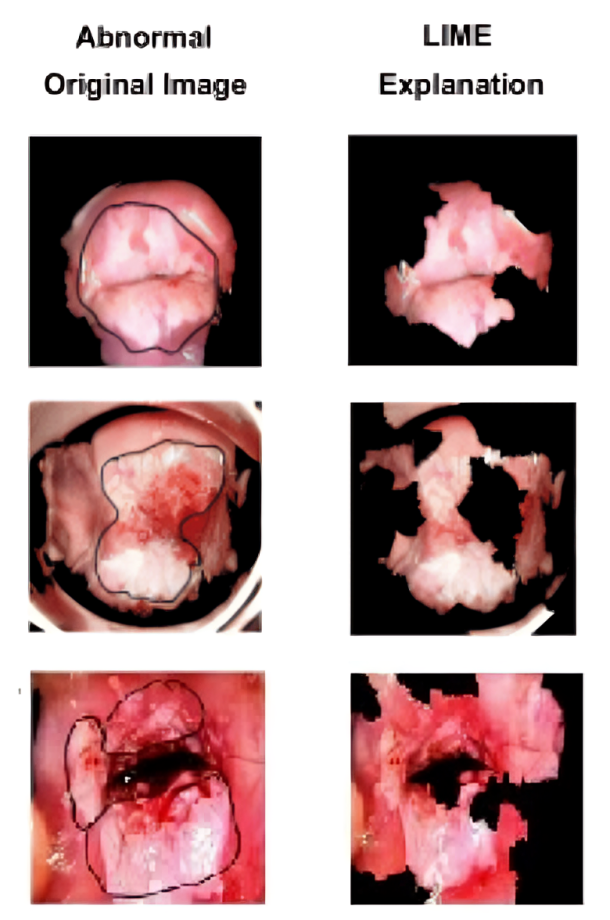

Among the two available datasets, the IARC dataset is used for the types classification, while the AnnoCerv dataset is used for the CIN score classification. Performing explainability on the types and the CIN score is difficult, as we cannot verify the type and the CIN score with naked eyes. Hence, the easiest way to verify the explainability results is to apply explainability to the abnormal images, which are also available in the IARC dataset. Due to computational constraints, we work with about one-third of such abnormal images [39].

For the LIME technique, the output is only in the form of one image where the region that has contributed to the decision-making of normal-abnormal is present in the image, and the region that has not contributed is blackened. If the marked cancerous region in the original abnormal image matches with the un-blackened region in the LIME image, then we say that is a correct explanation. In all the other cases, we say the explanation is incorrect. Algorithm 2 outlines the detailed step-by-step procedure of the proposed ensemble explainability method.

The results of this approach for about one-third of available abnormal images (122122) are presented in Table 12. As shown in the table, the first row highlights the performance of the SHAP technique, which independently provides correct explanations for 9696 images and incorrect explanations for 2626 images, achieving a performance of 78.68%78.68\%. The second row presents the performance of LIME, which independently generates the correct explanations for 9292 images and incorrect explanations for 3030 images, achieving a performance of 75.40%75.40\%.

The third row of the table lists the data for the collective performance I\mathrm{I}. Here, initially, LIME is applied, and then for those images where LIME fails, SHAP is applied. Thus, we achieve correct explanation for 117117 images (9292 images by LIME and 2525 images by SHAP) and incorrect for 55 images, achieving a performance of 95.90%95.90\%. Similarly, the fourth row of the table lists the data for the collective performance II\mathrm{II}. Here, initially, SHAP is applied, and then, for those images where SHAP fails, LIME is applied. Again, we achieve correct explanation for 119119 images (9696 images by SHAP and 2323 images by LIME) and incorrect for 33 images, achieving a performance of 97.54%97.54\%.

For the sake of exposition, we present a subset of images. Fig. 12(a) illustrates three cases where SHAP provides accurate explanations, while an additional eight images are included in Appendix A. Similarly, Fig. 12(b) shows three cases where LIME performs well, with eight more examples provided in Appendix B. All 122122 abnormal images used in this analysis are available in the shared drive333Google Drive folder containing all 122 abnormal images with explaaination. Since the region contributing to the decision in our classification model is correctly identified by our two ensemble XAI techniques in most of the cases, we can confidently say that our classification model performs correct classification.